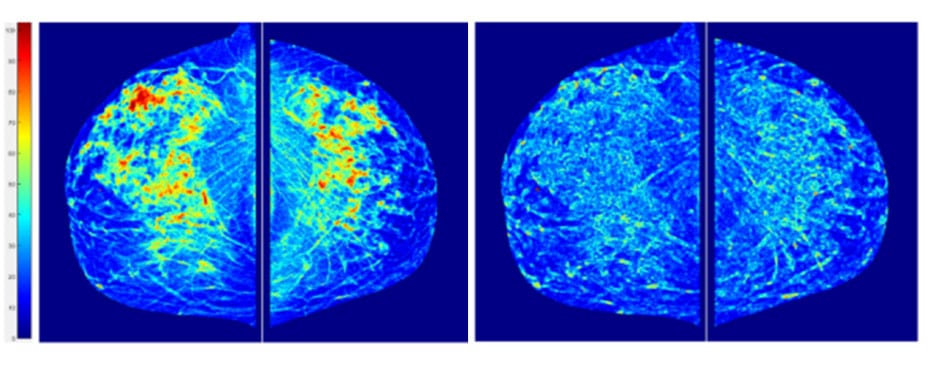

在不到20年的时间里,在快速发展的基于计算机的数字图像处理和机器学习技术的帮助下,用于乳腺癌成像、分类和诊断的技术有了显著的改进。自20世纪90年代计算机辅助诊断技术的早期发展以来,先后在匹兹堡大学和俄克拉何马大学任教的郑斌教授致力于[…]